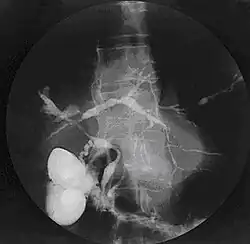

Cholangiogram of primary sclerosing cholangitis | |

Historically, a cholangiogram would be obtained via endoscopic retrograde cholangiopancreatography (ERCP), which typically reveals "beading" (alternating strictures and dilation) of the bile ducts inside and/or outside the liver. Currently, the preferred option for diagnostic cholangiography, given its noninvasive yet highly accurate nature, is magnetic resonance cholangiopancreatography (MRCP), a magnetic resonance imaging technique. MRCP has unique strengths, including high spatial resolution, and can even be used to visualize the biliary tract of small animal models of PSC.[22]